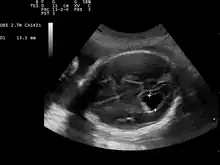

Ventriculomegaly is a brain condition that mainly occurs in the fetus when the lateral ventricles become dilated. The most common definition uses a width of the atrium of the lateral ventricle of greater than 10 mm.[1] This occurs in around 1% of pregnancies.[2] When this measurement is between 10 and 15 mm, the ventriculomegaly may be described as mild to moderate. When the measurement is greater than 15mm, the ventriculomegaly may be classified as more severe.[3]

This diagnosis is generally found in routine fetal anomaly scans at 18–22 weeks gestation. It is one of the more common abnormal brain findings on prenatal ultrasound, occurring in around 1–2 per 1,000 pregnancies.[4] In many cases of mild ventriculomegaly, however, there is resolution of ventriculomegaly during the pregnancy.

Although evaluation of lateral ventricles dimensions is decisive for establishing a diagnosis of ventriculomegaly, the shape of the ventricular system, including that of the frontal horns, is also important.[10]